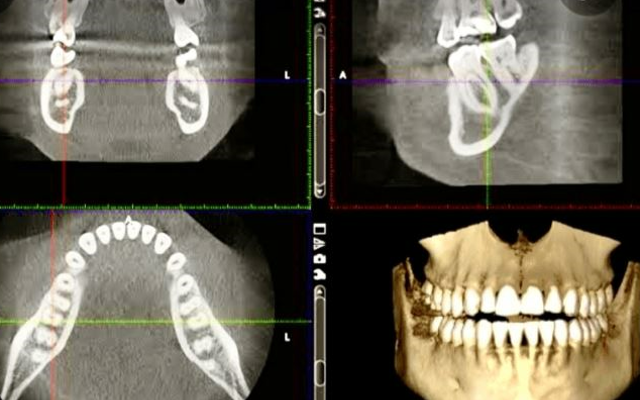

Cone Beam Computerised Tomography (CBCT):

A Cone Beam CT provides a 3-dimensional image of the teeth, the jaw bones, and the surrounding anatomical structures (Fig 19C). The 3-D view is particularly useful for planning the placement of dental implants as it will allow your periodontist to make accurate measurements of the volume of bone available for implant placement, how close the implant placement may be to nearby anatomical structures such as floor of the sinus, the nerve canals and to adjacent teeth. Cone Beam CT can be used to map out the pattern of loss of bone around the roots of the teeth for the purpose of complex treatment planning for periodontal diseases. It is also useful when there is more than one possible cause of bone loss around the roots of teeth- for example, a fractured root may be difficult to detect without 3-D imaging. Some periodontists will take CBCT scans in house with their own machine; others will refer you to a medical radiology clinic for the CBCT scan.